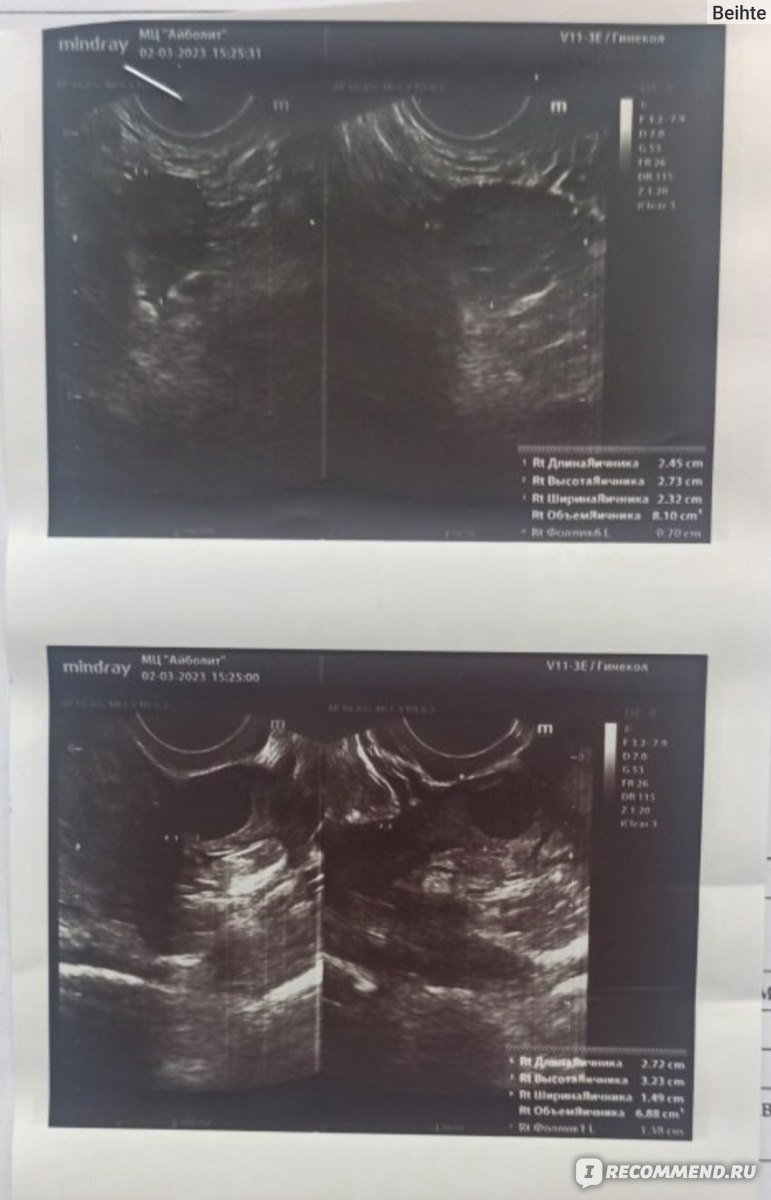

Эндометрий после кесарева